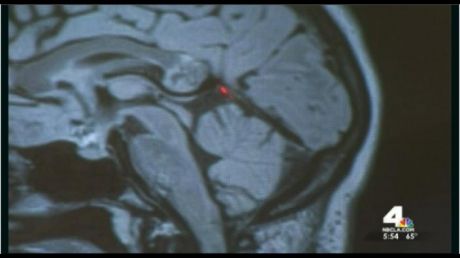

28 feb. 2016, 14:32ActualDescoperirea şocantă a chirurgului care a operat tumora pe creier a unei femei. Ce era, de fapt

23 apr. 2015, 10:24LifestyleDescoperirea şocantă a chirurgului care a operat tumora pe creier a unei femei. Ce era, de fapt